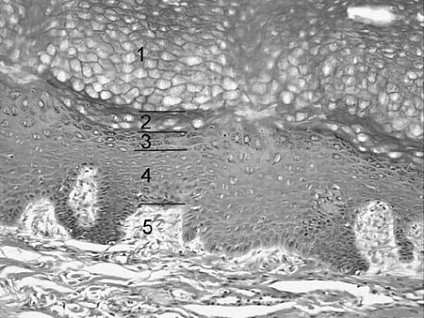

During a routine physical examination, you notice that your patient, a 35-year-old avid surfer, has spots of abnormal pigmentation on two of her fingers. You explain to your patient that long-term exposure to the sun increases the risk of neoplastic changes and that you would like to perform biopsies to verify the nature of the abnormal pigmentation. Referring to following figure, cells from which layer of the epidermis are most vulnerable to neoplastic changes due to long-term exposure to the sun?

Long-term exposure to the sun increases the risk of alteration of the DNA structure by cleavage, ionizing radiation, or recombination of DNA with highly reactive free radicals. These changes can result in neoplastic changes or death in skin cells. In the skin, mitosis occurs only in the malpighian layer formed by the stratum basale and the stratum spinosum of the epidermis. The DNA of dividing cells is more vulnerable to the harmful effects of the sun, and neoplastic changes are usually observed in the Malpighian layer. They are not seen in the stratum corneum (choice A), stratum lucidum (choice B), or stratum granulosum (choice C). Choice E represents the dermis located below the epidermis, which is the only skin layer considered in this question.